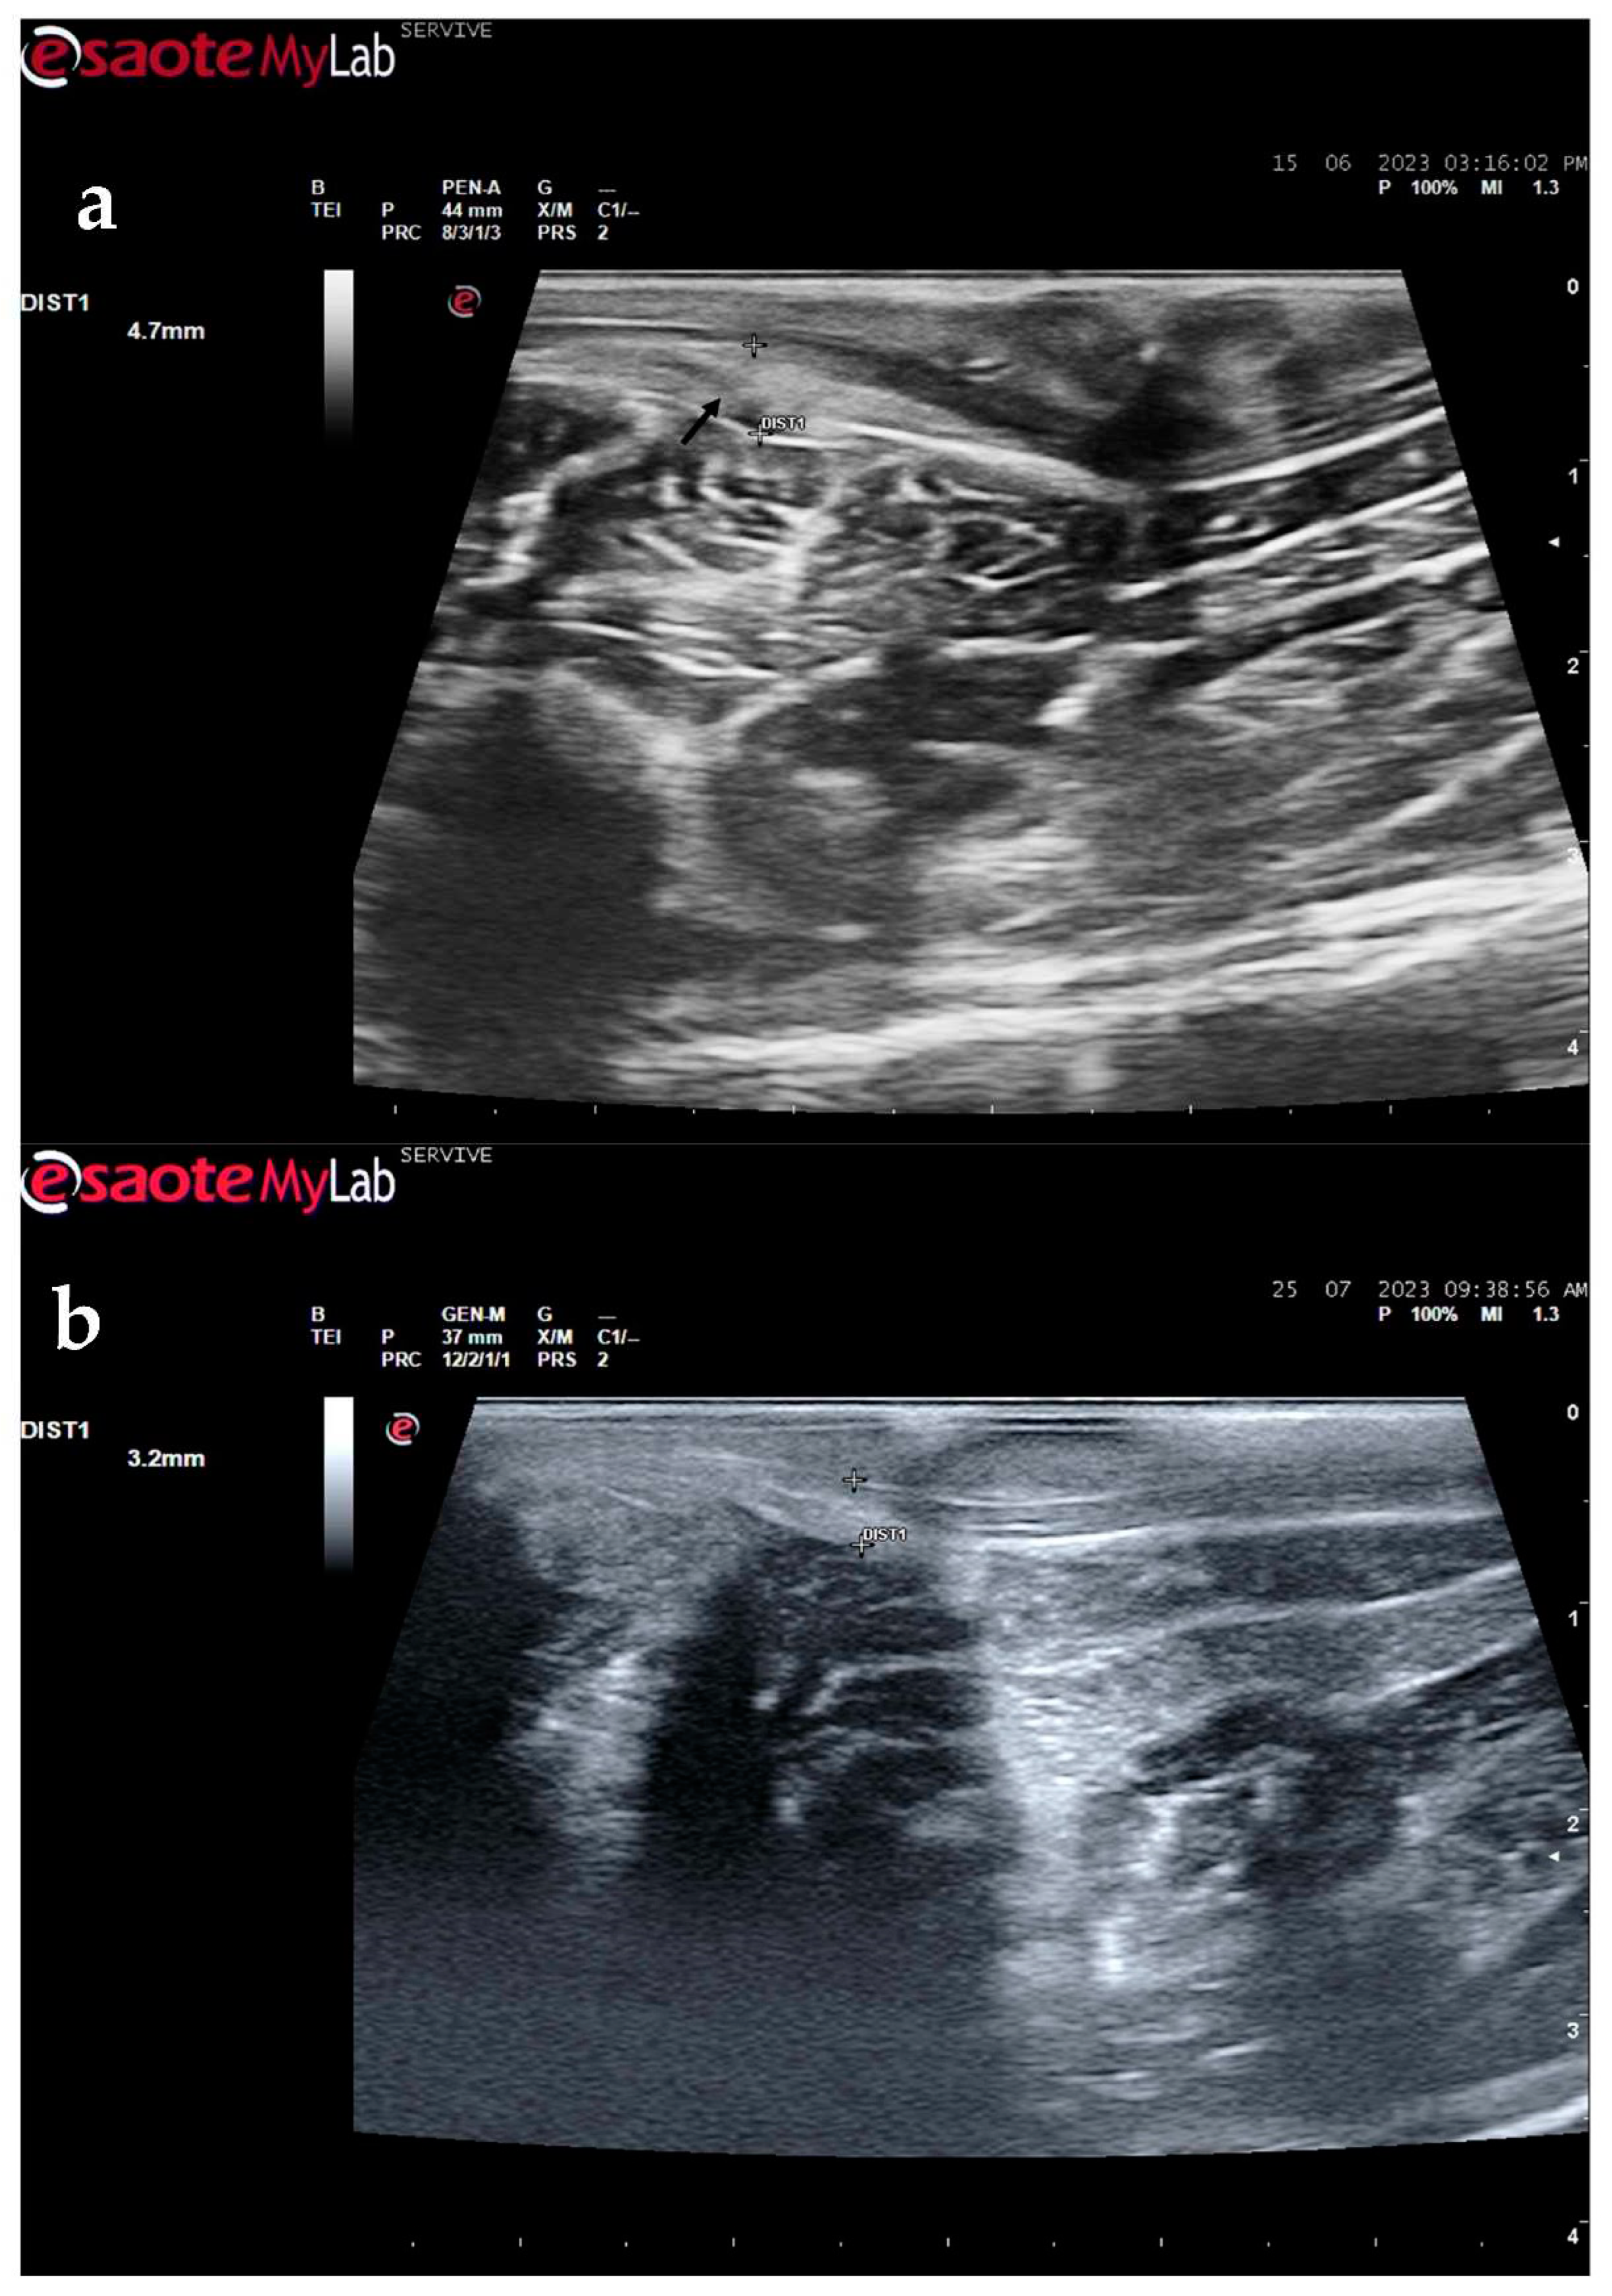

The described technique allows an easy follow-up of the progression of nerve regeneration over time after the induction of a lesion in a controlled surgical environment. For example, after application of a tube guide, in which the nerve tops of a transected nerve are sutured to the ends of the tube, leaving a gap to be filled inside the biomaterial, immediately after surgery it is possible to identify the tube guide and the nerve tops inside of it by ultrasound (

Figure 9). The tube guide appears as a hyperechogenic structure, at the ends of which the nerve tops are observed (

Figure 9a), allowing the measurement of the created gap and its evaluation and measurement over time until the total closure and reconnection of the nerve ends (

Figure 9b). In the same way, after the application of end-to-end sutures, in which the ends of the transected nerve are coapted and sutured in order to guarantee the their reconnection and anatomical continuity, it is possible to observe the nerve continuity echographically (

Figure 9.

Ultrasound image of the left peroneal nerve in a sheep subjected to a transection lesion followed by the application of a tube guide. (a) after 1 week, it is possible to observe the tube guide as a hyperechogenic tubular structure (black arrows) at the ends of which the ends of the transected nerve are inserted (white arrows). DIST1 represents the length of the gap left between the two nerve ends; (b) after 3 months, the tube continues to be perfectly visible (black arrows), as well as the nerve introduced into its lumen (white arrows), but now, instead of the gap between the nerve tops, an anatomical continuity of the nerve is observed along the entire tubular lumen (beige arrow), indicating a nerve reconnection. In the center of the tubular lumen, a hypoechoic space not filled by nervous tissue is also observed (brown arrow), indicating that the regenerating nerve has not yet occupied all the available space inside the tube guide. DIST1 represents the nerve diameter and DIST2 represents the inner diameter of the tube guide.